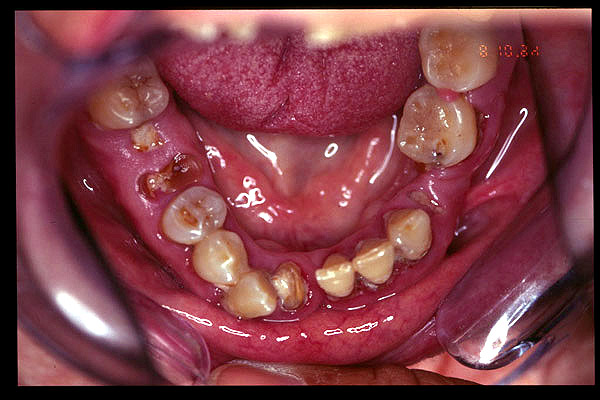

CM Desgaste por bruxismo, presencia de cálculo